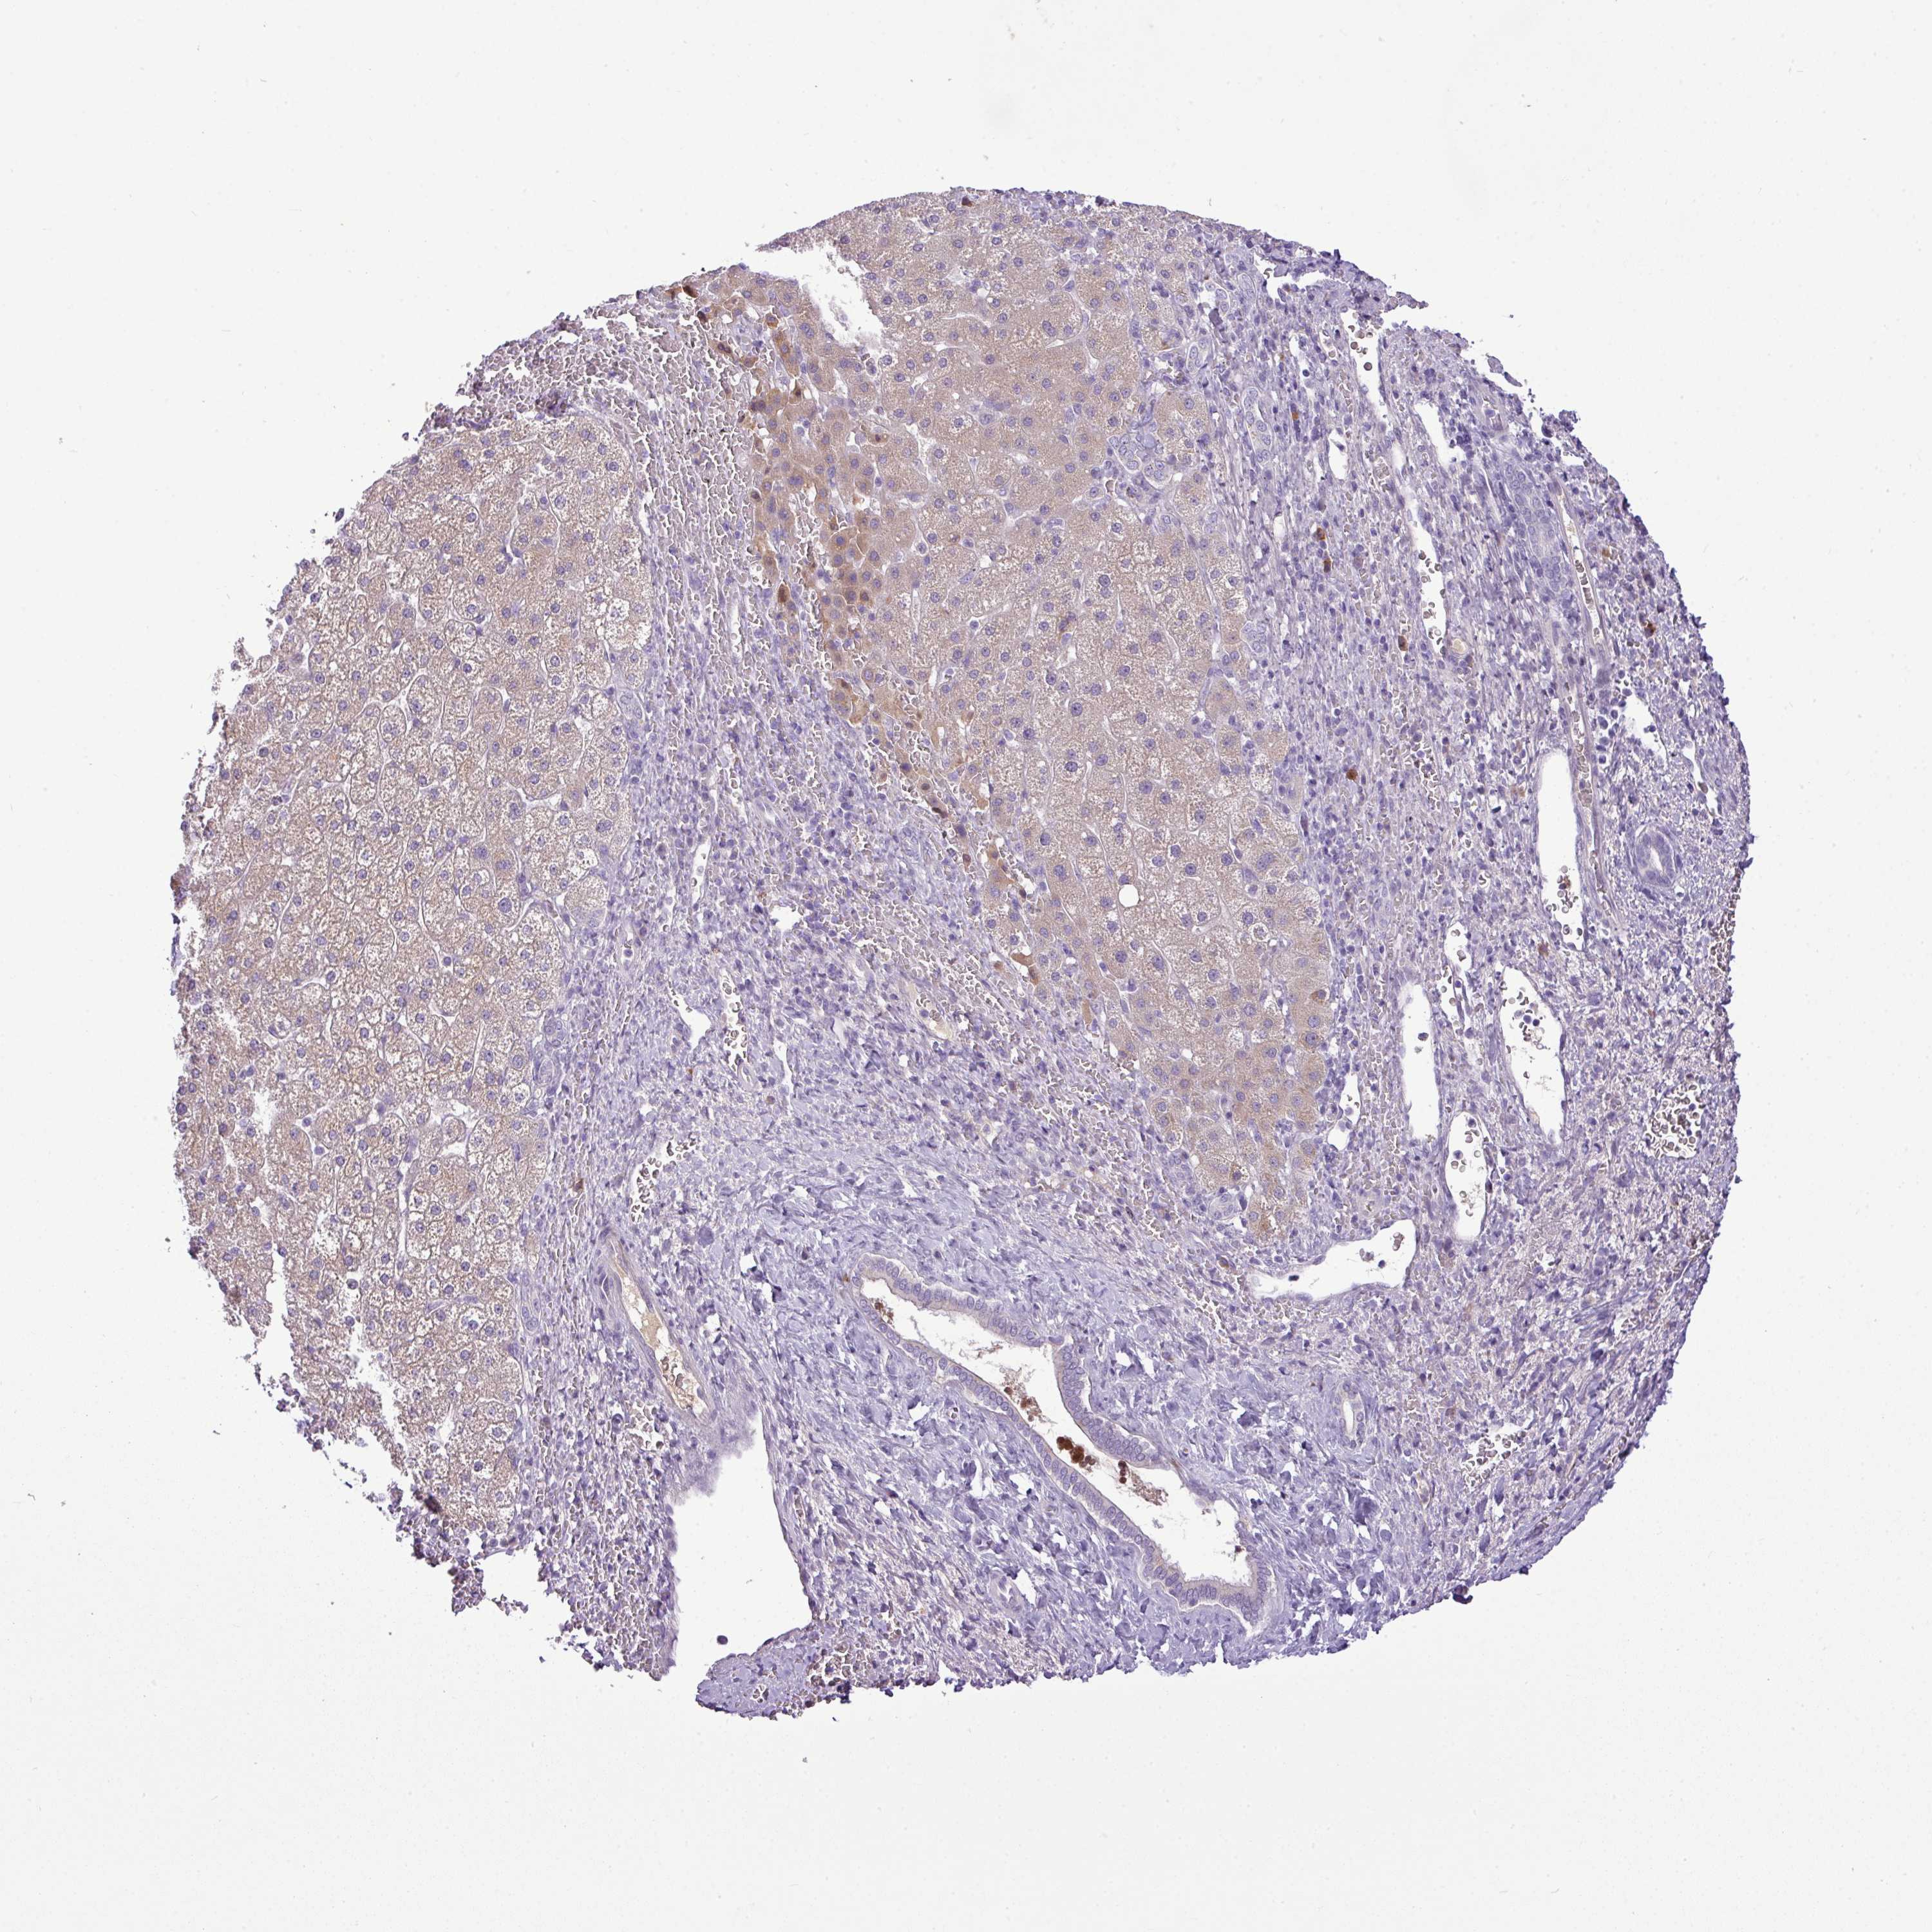

LIVER CANCER - Protein expressioni

A mouse-over function shows sample information and annotation data. Click on an image to view it in a full screen mode. Samples can be filtered based on level of antibody staining by selecting one or several of the following categories: high, medium, low and not detected. The assay and annotation is described here.

Note that samples used for immunohistochemistry by the Human Protein Atlas do not correspond to samples in the TCGA dataset.

Antibody stainingi

Antibody staining in the annotated cell types in the current human tissue is reported as not detected, low, medium, or high, based on conventional immunohistochemistry profiling in selected tissues. This score is based on the combination of the staining intensity and fraction of stained cells.

Each image is clickable and will lead to virtual microscopy that enables deeper exploration of all samples and also displays staining intensity scores, fraction scores and subcellular localization as well as patient and tissue information for each sample.

HPA046356

HPA048287

HPA050103

CAB009811

CAB032603

Staining

High

Medium

Low

Not detected

Intensity

Strong

Moderate

Weak

Negative

Quantity

>75%

75%-25%

<25%

None

Location

Nuclear

Cytoplasmic/membranous

Cytoplasmic/membranous,nuclear

Cholangiocarcinoma

Carcinoma, Hepatocellular, NOS